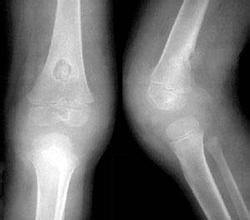

主要為X線平片檢查,於病變骨幹周圍可有新骨形成,多呈蔥皮樣增生。新骨內或髓腔內可有溶骨性破壞區,呈單發或多發,以橢圓形多見,但死骨少見。結核性骨膜炎僅有局限性骨膜增生而不伴有破壞征。